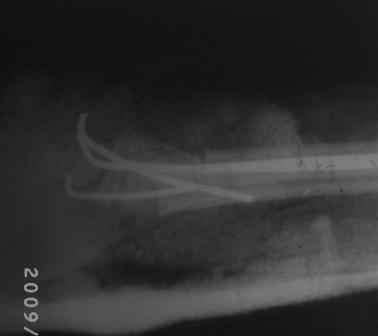

19.08.09г, на форуме был представлен случай: мальчик.13 лет, с артрогрипозом. Позже Евгений Чекашкин просил представить результаты лечения, поэтому , как раз больной на днях пришел для снятия гипсовой повязки, и решил показать что случилось. Оперировал 1,5 месяц назад, транспозиция сухожилий лучевой и локтевой сгибателей на тыл,тенотомия ладонного сухожилия, укорачиваюшая остеотомия костей п/плечья в дистальной трети,фиксация спицами в положении экстензии 15гр. После снятия гипса разгибание пальцев хорошие, сгибание ограничены, назначены ФТЛ, массаж и ЛФК, Больной и родители довольны результатом, я сам не очень! Фото и Р-снимки прилагается. Хочу выразить благодарность Ольге Агранович, А. Челнокову, Е. Чекашкину,Устьянцев Ибрагимову, ПОЗДРАВИТЬ ВСЕХ С НАСТУПАЮШИМ НОВЫМ ГОДОМ! С уважением Абдурашид.

Волярный наклон суставной фасетки лучевой кости в норме составляет 9 градусов, а у вашего пациента фасетка наклонена на 40 градусов в тылную сторону, это значит что угол смещения равен 49 градусам.

Нужно повторить снимки лучезапястного сустава в 2х проекциях, т.к. предоставленные снимки не качественные, они нужны для изучения радиоульнарного угла и дистального радиоульнарного сустава, это очень важно.